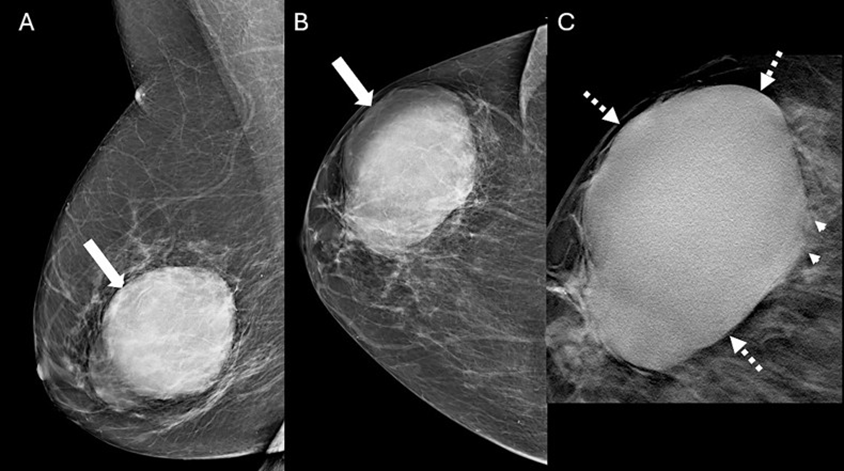

Figure 1: Mammogram images of a 77-year-old female with a palpable lump. Mediolateral oblique (A) and craniocaudal (B) mammogram images of the right breast demonstrate an 8.2 cm, oval, high-density, non-calcified mass (arrow) with predominantly circumscribed margins in the lateral aspect of the breast, anterior and middle depths. The circumscribed margins (dashed arrows) and subtle indistinct margins (arrowheads) are best appreciated on the spot tomosynthesis image (C). The left breast is normal (not shown).

The mammogram showed an 8.2 cm, oval, high-density, non-calcified mass with predominantly circumscribed margins in the lateral aspect of the right breast (Figure 1). The left breast was normal. Targeted Ultrasound (US) of the right breast demonstrated an 8.0 cm, oval, parallel, heterogeneous mass with indistinct margins and posterior acoustic enhancement. Internal vascularity was present (Figures 2,3). The mass was assessed as a BI-RADS 4 lesion. US-guided biopsy of the mass was subsequently performed.

On mammography, PMC typically presents as an oval/round, equal to high-density mass with circumscribed or microlobulated margins [1,2,7]. Spiculated or indistinct margins are more indicative of MMC secondary to the IBC-NST component [1,2,7]. The ultrasound appearance of PMC is often as an oval/round mass with microlobulated or indistinct margins with variable echogenicity, ranging from isoechoic to mixed solid and cystic [1,2,7]. Posterior acoustic enhancement is often present due to high mucin content [1,2,7]. MRI features of PMC are of an oval/ round T1-hypointense, T2-hyperintense (due to mucin) mass often with rim or heterogenous enhancement [1,2,7,8]. Due to favorable histology, PMC is treated by surgical excision without nodal sampling [1]. Adjuvant endocrine therapy is recommended to decrease the risk of local recurrence and distant metastasis [1]. PMC has a low recurrence rate of 6.2% [1].